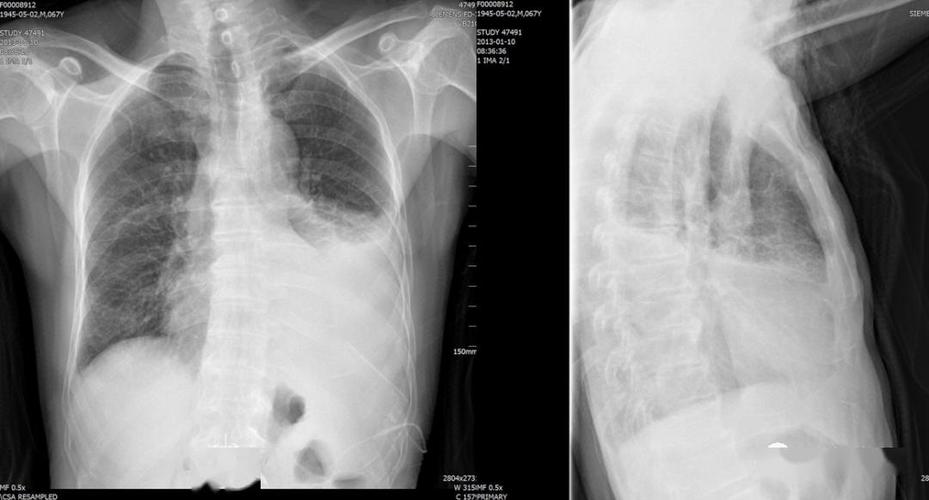

肺不张影像图片,肺不张影像

肺不张的影像学

供临床医学大专医学影像诊断用 2,肺不张 ——支气管完全阻塞时,气体

肺不张:影像基本思路

肺不张影像表现

肺不张影像学表现

肺不张胸片表现

肺不张x线表现